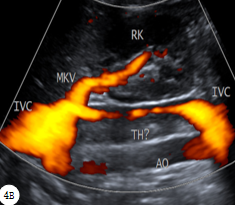

河北医科大学第二医院   东院区超声科  赵雅培患儿女,13岁,因“腰痛伴发热5天、呼吸困难3天”就诊。患儿于5天前无明显诱因出现腰痛,为持续性胀痛,伴发热,无心慌、乏力,无尿频、尿急,于3天前就诊于当地县医院。腰椎正侧位示:腰椎骨质结构未见异常。超声检查:肾脏未见异常,下腔静脉血栓(图1)。肺部CT示:双肺片状渗出(肺炎)。遂行经颈静脉穿刺置管溶栓术、抗感染,患者症状未改善,为进一步诊治遂入我院。急查超声并完善各种检查,下腔静脉超声:①下腔静脉溶栓导管(图2A)②下腔静脉肾静脉水平以下血栓伴管腔重度狭窄(较溶栓前范围明显延伸,图2B)。WBC 2.90×109/L,N 91.69%;CRP 191.8mg/L,FDP 91.81ng/L,D二聚体 7.6ug/ml。血培养:金黄色葡萄球菌阳性。考虑患儿“重症肺炎、脓毒症、下腔静脉血栓伴脓栓”诊断成立。考虑溶栓导管术后疾病进展,遂拔除颈静脉置管,静脉注射人免疫球蛋白支持治疗,中和免疫介质,调节免疫力。患儿住院第6天,体温较前升高,最高达38.8℃,间断诉胸闷、呼吸困难,伴烦躁,腰痛;WBC 15.08×109/L,N 93.42%;CRP 286.00mg/L,FDP 15.07ng/L,D二聚体 1.35ug/ml,抗凝治疗有效。肺部CT:两肺广泛多发团、片状结节,部分病变内见小空洞,考虑多发感染(图3A)。追问病史,患儿于1月前面部疖肿,累及范围较大、位置较深,有挤压史,迁延自愈,故金黄色葡萄球菌感染来源及诊断明确。患儿住院第16天,体温恢复正常,阵发性咳嗽伴右侧胸痛,偶诉腰痛。胸部螺旋CT:两肺内多发球形或团状病变及大部形成空洞或空腔,大部病变空洞内壁较为光滑,壁厚而不均匀;左肺气胸(图3B)。超声:下腔静脉肾静脉以下血栓伴重度狭窄(较入院时略有缩窄,图4A~B)。继续抗感染、抗凝治疗;发病第53天彩超:下腔静脉肾静脉水平以下附壁陈旧性血栓(较前明显缩小,图5);3个月彩超:下腔静脉血栓消失。 图1  溶栓前下腔静脉血栓  图2  A:下腔静脉溶栓导管;B:溶栓3天后下腔静脉血栓;图3  A:住院第6天两肺广泛多发团、片状结节,部分内见小空洞;B:住院第16天两肺多发球形或团状病变,大部形成空洞或空腔;左肺气胸  图4  住院第16天A:下腔静脉血栓;B:彩色多普勒能量图下腔静脉管腔内窄带状血流信号  图5 发病第53天下腔静脉后壁陈旧性血栓(IVC:下腔静脉,AO:腹主动脉,RK:右肾,TH:血栓,MKV:主肾静脉,RKV:右肾静脉)讨论  下腔静脉血栓(inferior vena cava thrombosis,IVCT)是一种比较严重且危急的疾病,可导致急性肺栓塞而危及患者生命[1]。众所周知:炎症和血栓不是相互独立的病理过程,一方面炎症促进血液高凝状态,易导致血栓形成;另一方面血栓形成中的物质也可引起炎症;二者相互作用、恶性循环。导管接触性溶栓(catheter-directed thrombolysis,CDT)是导管置于血栓内部,增加溶栓药物与血栓的接触面积,全程作用于血栓内部,增加局部药物浓度,提高溶栓效率,避免短时大剂量应用溶栓药物带来的出血等风险,使溶栓效果更确切、安全有效[2]。本病例溶栓后血栓大面积延伸、脓毒血症发生,分析原因有二:一是溶栓前患儿已有感染症状、金葡菌阳性,白细胞低、免疫力低下;二是溶栓后,导管进入血栓内部,会导致血栓物质与炎症因子的进一步结合,加速血栓发展、形成严重的全身化脓性感染。另外,对于无明确伴发炎症的IVCT,进行CDT必须在置管过程保证严格无菌操作,以防出现导管内感染、脓毒症发生。脓毒症指由感染引起的全身炎症反应综合征,可由身体任何部位感染导致,如蜂窝织炎、脓肿、脑膜炎等,常出现明显肝功能受损[3];本患儿感染来源于面部疖肿既往史。WBC是重要的血细胞,具有吞噬异物的作用,可抵抗病原体入侵。吴青等指出WBC计数检测结果易受机体免疫、应激、疾病等多种非感染性因素影响,如免疫力低下的患儿细菌感染严重时WBC计数升高也不明显,对疾病状态无法正确评价[4]。该患儿初期WBC低于正常水平,后经正常至显著升高,与上述解释一致。下腔静脉内占位病变包括血栓、癌栓、肿瘤及假性病变等,以血栓最为常见。该患儿既往体健,结合病史可以明确下腔静脉血栓。血栓早期为急性、亚急性期,灰阶超声表现为极低回声或低回声,管径相应增宽;慢性期则表现为中等回声或钙化强回声,管径变细。彩色超声示血栓内无血流信号,与管壁分界不清[5]。该病例住院前县医院超声检查、住院后急诊床旁超声检查,灰阶模式声像图表现由团状高回声转归为长带状不均匀低-高回声(图1,2B),虽不影响血栓诊断,但受仪器条件限制管壁与管腔显示欠清晰。后两次检查均使用大型超声诊断仪采集声像图,血栓由带状等回声转归为带状高回声,管壁与管腔清晰度明显提高(图4A,5)。彩色多普勒能量图(CDE)是一种以能量模式显示的血流成像技术,具有更高的血流敏感性,尤其是显示流速较低的静脉边缘血流,血流充盈度更真实(图4B)。综上所述,超声医生在诊断中应该详细追问病史、结合实验室,明确诊断是单纯性血栓,还是血栓伴脓栓,为临床医生实施CDT治疗提供可靠依据。参考文献[1] 张志文,陈学明,冯海,李晨宇,于宏志,张忠涛.临时滤器联合经导管血栓抽吸术和导管接触性溶栓治疗下腔静脉血栓[J].中国血管外科杂志(电子),2020,12(3):222-226.DOI:10.3969/j.issn.1674-7429.2020.03.011[2] Wang L,Zhang C,Mu S,et al.Safety of catheter-directed thrombolysis for the treatmentof acute lower extremity deep vein thrombosis:a systematic review and meta-analysis[J]. Medicine, 2017, 96(35):e7922.DOI:10.1097/MD.0000000000007922.[3] 张韬,张丽娟,王红霞.脓毒症患者病原学特征、肝功能及sTREM-1水平分析[J].中国病原生物学杂志,2019,14(06):710-712.DOI:10.13350./j.cjpb.190619.[4] 吴青,柴建农,徐咏梅,等.常用检验指标在无明显感染灶幼儿急性发热诊断中的价值[J].临床儿科杂志,2015,33(05):454-458.DOI:10.3969j.issn.1000-3606.2015.05.014.[5] 宋奕宁,赵艺超,李建国.下腔静脉肿瘤的超声影像诊断与鉴别[J].中国超声医学杂志,2018,34(1):37-39.DOI:10.3969/j.issn.1002-0101.2018.01.012.